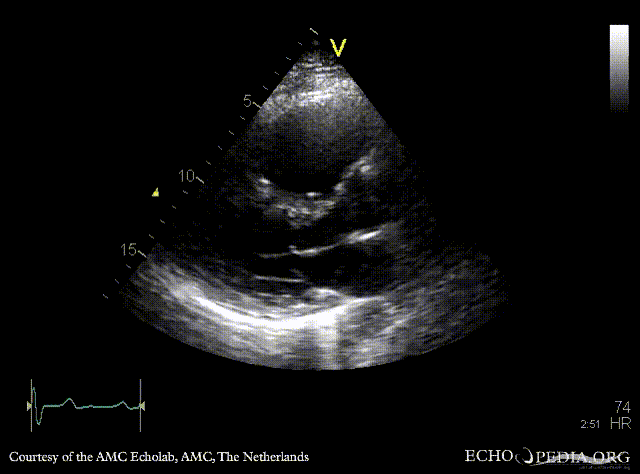

E00308.gif E00309.gif

PLAX: right ventricle enlargement in patient with ASD type II PSAX: right ventricle enlargement and diastolic flattening of the IVS